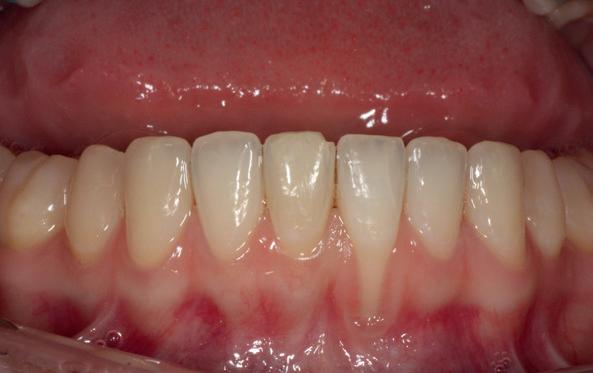

Een 48-jarige gezonde vrouw presenteerde zich in de nazorgfase 2 jaar na initiële behandeling met pockets van 6–7 mm en furcatieproblematiek bij de 47 en 46 (afbeelding 1.1 en 1.3). Bloeding bij sonderen was aanwezig, maar de patiente wilde geen chirurgische behandeling. Ze hield er een keurige mondhygiëne op na en kwam trouw iedere drie maanden voor nazorg.

De pockets werden onder lokale anaesthesie behandeld met een combinatie van ultrasoon en handinstrumentarium volgens de hierboven beschreven methode. De natriumhypochloriet/aminozuur-gel werd vijfmaal aangebracht en na iedere applicatie mechanisch verwijderd. Daarna werd de pocket gevuld met cross-linked hyaluronzuur.

Na 6 maanden was de pocketdiepte teruggebracht tot 3 mm en was er geen bloeding na sonderen waarneembaar. Een recessie van 2 mm was aanwezig. Röntgenologisch was er nieuw bot zichtbaar (afbeelding 1.2 en 1.4).